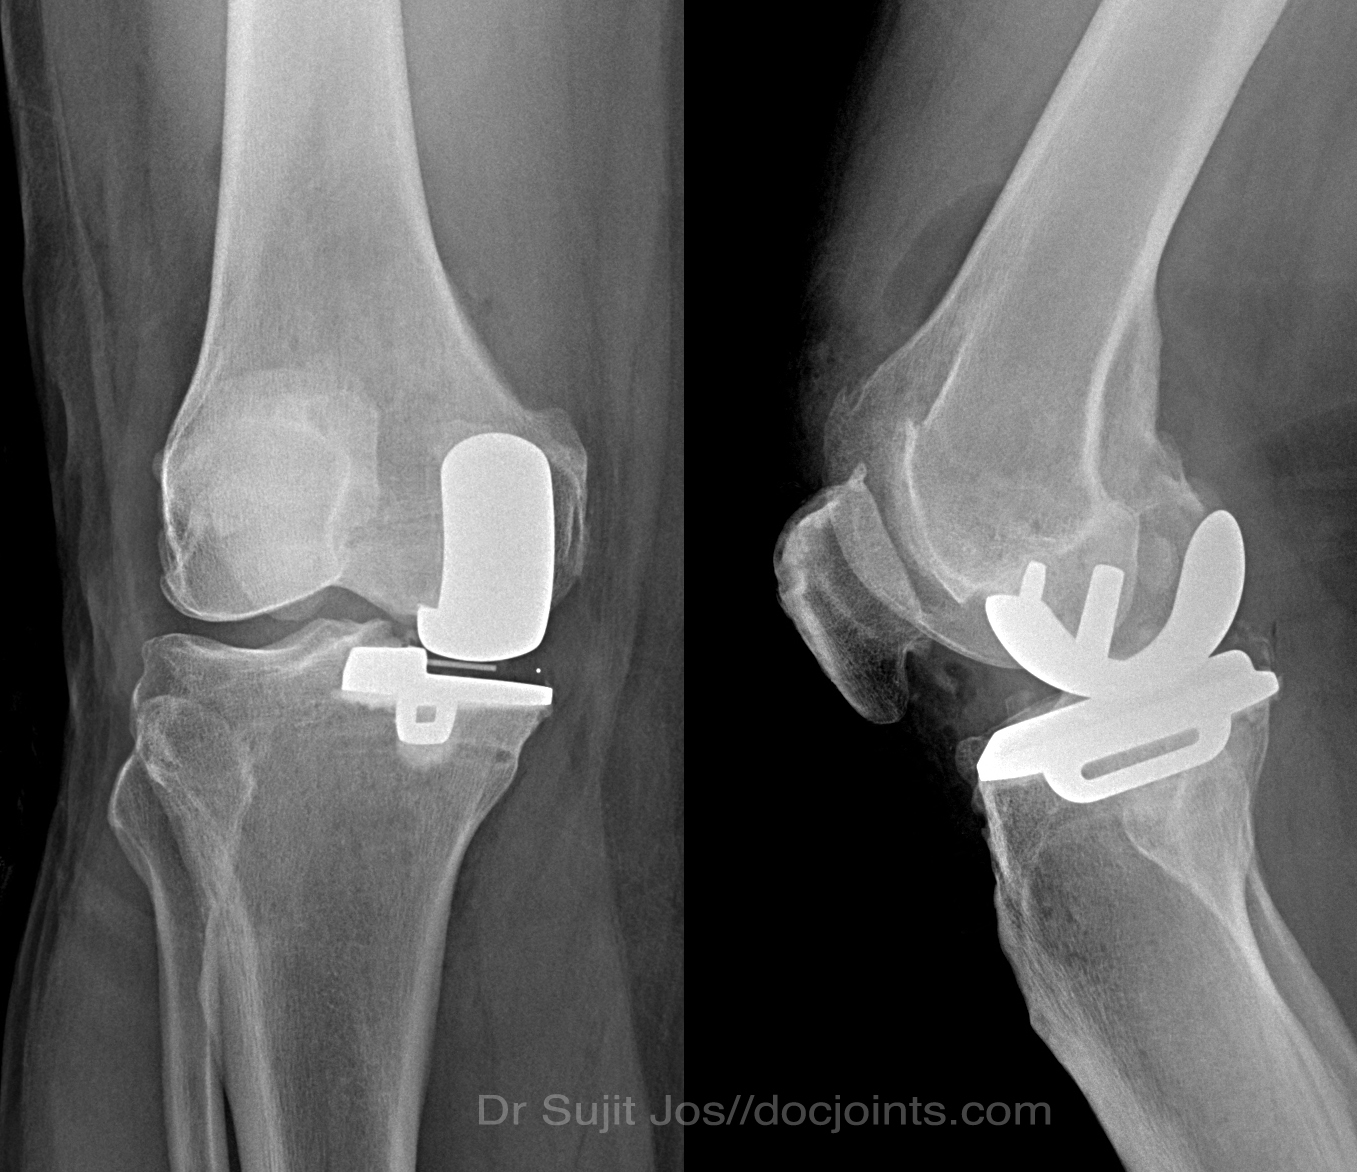

Unicondylar Knee Replacement

Xray after unicompartmental knee replacement